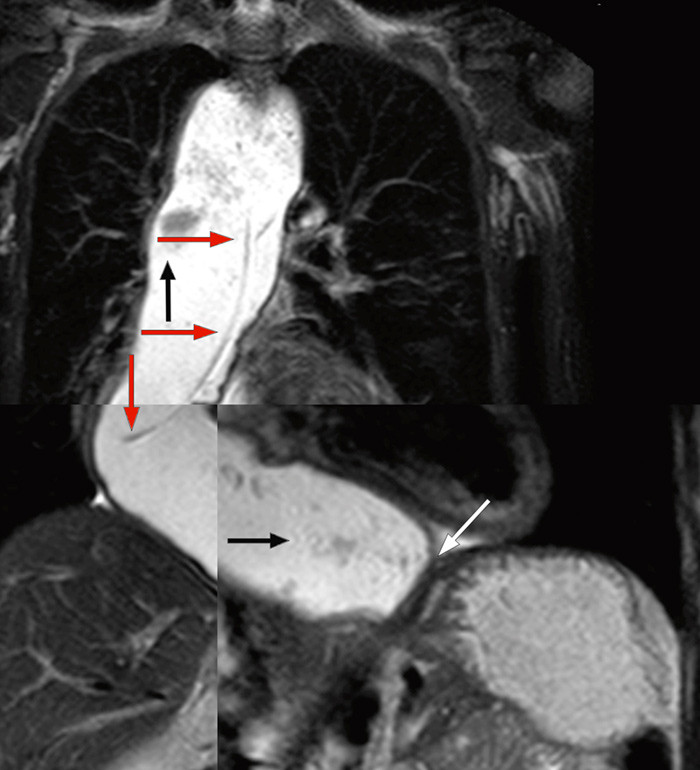

Vi mistenkte nå oesophagusakalasi. Luften som var projisert over mediastinum ved innkomst (fig 1), var sannsynligvis luft i en dilatert oesophaugus og ikke uttrykk for pneumomediastinum, som først antatt. MR oesophagus viste slynget og dilatert (> 6 cm proksimalt) oesophagus med innhold, stenose ved overgangen til ventrikkel og små bilaterale lungefortetninger. Det var bildemessig ikke mistanke om stenoserende malignitet (fig 2).

Det radiologiske bildet viste før terapi en distal oesophagus med et mer konisk utseende (fuglenebb). Etter diskusjon ønsket vi først å forsøke blokking av nedre sphincter med klassisk akalasiballong. Kvinnen har vært observert i 36 uker etter én blokking. Hun spiser normalt og har hatt vektøkning på > 10 kg.